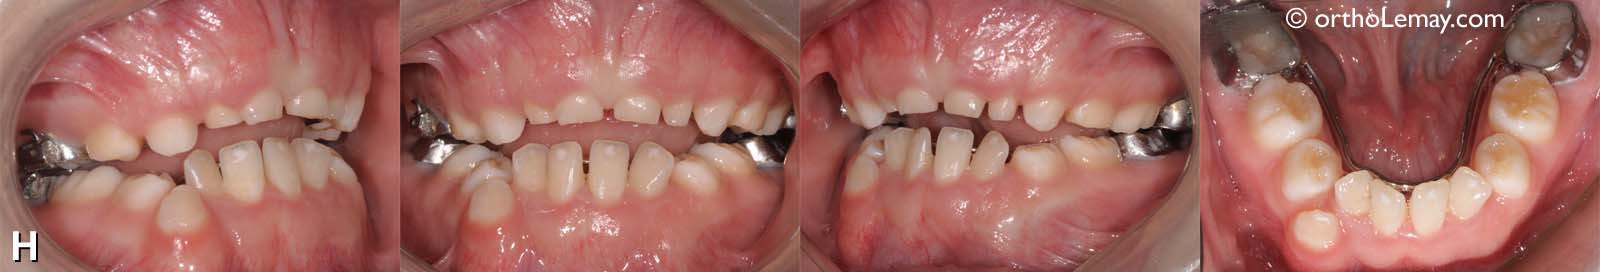

H) Malocclusion

(H) Résultat final: les deux arcades ont été élargies significativement et le tout est maintenu avec des mainteneurs d’espace à chaque arcade en attendant l’éruption des autres dents permanentes, ce qui prendra encore quelques années.

À noter qu’il aurait été possible d’obtenir encore plus d’espace pour la langue en alignant les dents antérieures inférieure en les déplaçant vers l’avant mais cette étape ne fut pas envisagée car le traitement avait déjà été long et complexe pour cette jeune patiente.